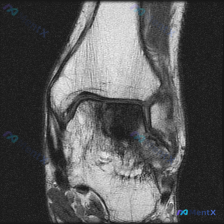

今天遇到一个挺典型的临床情况,整理出来和大家聊聊:核心问题是临床观察提示「软骨异常」,但我们拿到的单幅膝关节MRI冠状位T2加权像分析却全是阴性结果,一起来理理思路。 先给大家放完整影像信息: 1. 整体结构对位:股骨远端胫骨近端对位正常,无骨折错位 2. 骨髓信号:股骨髁、胫骨平台骨髓信号大致均匀...

刚梳理完一份膝关节MRI读片病例,核心问题是「这张图像中可视觉识别的潜在异常是什么?」,标准答案提示是软骨异常,不过整理完发现这个病例其实挺值得讨论,分享一下完整分析思路。 病例影像基础信息 这是一张膝关节MRI冠状位影像,我们先整理客观观察到的所有征象: 1. 骨骼结构:股骨远端、胫骨平台骨皮质连...